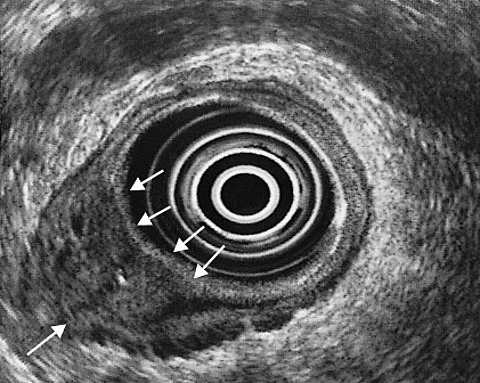

Seit einigen Wochen hatte die Patientin helles Blut im Stuhl. Bei der Prokto-Rektoskopie hatten Sie einen ulzerierten, blutenden Prozess gefunden. Die Histopathologie bestätigte den Verdacht.